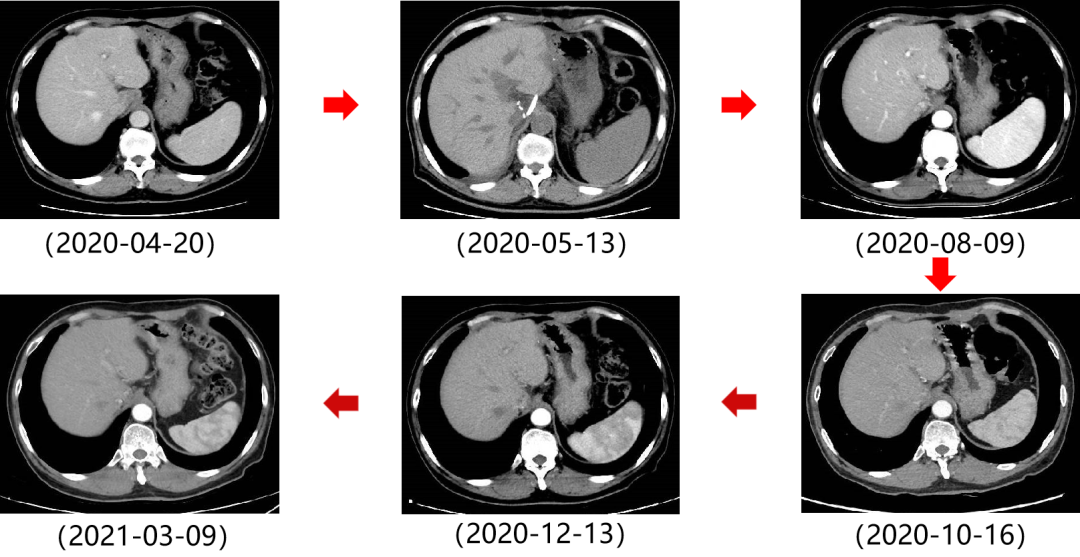

二 病例分享 专家简介 01 基本情况 患者:汪XX,男,63岁。身高 165cm;体重 65kg;体表面积 1.70m2;ECOG 1分。 主诉:反复解黏液血便3天。 对磁共振造影剂过敏,无食物、其他药物过敏史。既往史、个人史、婚育史、家族史均无特殊,无吸烟、饮酒史。 02 初诊病史 现病史:患者2017年3月初无明显诱因下解黏液血便,量中等,为鲜血,反复发作,无恶心、呕血、黑便、腹痛、腹泻、里急后重等不适。遂于2017年3月初就诊我院。 胸、腹、盆腔CT平扫+增强:乙状结肠肠壁明显增厚,肠腔狭窄,增强期强化明显;肝脏多发低密度病灶,增强期不规则强化,考虑乙状结肠癌伴肝脏多发转移。 03 治疗方案 【一线治疗】 2017-06-22 西妥昔单抗+FOLFIRI* Q2W×3 西妥昔单抗 900mg ivgtt D1; 5-氟尿嘧啶 0.6g iv D1,3.5g civ 48h; 亚叶酸钙 0.6g ivgtt D1; 伊立替康 280mg ivgtt D1。 第1疗程结束后黏液血便较前消失,过程顺利,耐受良好,无皮疹、腹泻等不良反应,治疗10疗程,疾病进展。 疗效评估-影像学(部分缓解,PR)。 2017-07-15 乙状结肠癌切除术* 手术记录:肿瘤位于乙状结肠,大小约4cm×3cm,未突破浆膜层,病灶周围可及数个稍肿大淋巴结,未及盆底种植结节。 手术过程顺利,术后恢复良好。 术后病理:(乙状结肠)中分化腺癌,浸润肠壁浆膜下层,两切缘阴性,未见脉管癌栓及神经束侵犯,LN 2/18(+) 2017-08-20 肝转移瘤切除术* 手术记录:肝脏肿瘤位于肝右叶,大小分别约2cm×1.5cm,1cm×1.2cm,其余肝表面未见异常结节,腹腔无腹水、无粘连。 手术过程顺利,术后恢复良好。 术后病理:(肝右叶病灶)中分化腺癌,结合临床病史,符合乙状结肠癌肝转移,肝组织切缘未见癌。 疗效评估-影像学(NED)。 2017-11-06 西妥昔单抗+FOLFIRI* Q2W×3 西妥昔单抗 900mg ivgtt D1; 5-氟尿嘧啶 0.6g iv D1,3.5g civ 48h; 亚叶酸钙 0.6g ivgtt D1; 伊立替康 280mg ivgtt D1; 过程顺利,无皮疹、腹泻等不良反应。每疗程后均予PEG-CSF预防性升白,耐受良好。 疗效评估-影像学(病情进展,PD1)。 胸、腹、盆腔CT平扫+增强:肝左外叶低密度灶,增强期不规则强化,结合病史,考虑结肠癌肝转移,余未见明显异常。 【二线治疗】 2018-03-06 肝左外叶肿瘤切除术* 术中探查见:肿瘤位于肝左外叶,质硬,边界不清,余肝脏表面未见异常结节灶,腹盆腔无腹水。 手术过程顺利,术后恢复良好。 术后病理示:(肝左叶)中分化腺癌,结合临床病史,符合结肠腺癌肝转移。 2018-04至2018-07 卡培他滨+奥沙利铂* Q3W×5 卡培他滨 1.5g BID D1-14; 奥沙利铂 200mg ivgtt D1。 过程顺利、耐受良好,无腹泻、神经毒性等不良反应。 疗效评估-影像学(病情进展,PD2)。 胸、腹、盆腔CT平扫+增强:肝尾状叶结节状异常密度灶,增强期不规则强化,结合病史,考虑结肠癌肝转移,余未见明显异常。 2018-07至2020-04 贝伐珠单抗+卡培他滨* Q3W×21 贝伐珠单抗 500mg ivgtt D1; 卡培他滨 1.5g BID D1-14。 过程顺利、耐受良好,期间曾出现II度腹泻,对症治疗后可恢复正常。无血压升高、出血、蛋白尿、手足皮肤反应。 疗效评估-影像学(最佳疗效,PR)。 疗效评估-影像学(病情进展,PD3)。 腹腔镜肝尾状叶切除术+腹腔粘连松解术* 术中探查见:肿瘤位于肝尾状叶,质硬,边界不清,余肝脏表面未见异常结节灶,腹盆腔无腹水。 手术过程顺利,术后恢复良好。 术后病理示:(肝尾状叶)中分化腺癌,结合临床病史,符合结肠腺癌肝转移。 2020-06至2021-09 贝伐珠单抗+卡培他滨* Q3W×16 贝伐珠单抗 500mg ivgtt D1; 卡培他滨 1.5g BID D1-14。 过程顺利、耐受良好,期间曾出现II度腹泻,对症治疗后可恢复正常。无血压升高、出血、蛋白尿、手足皮肤反应。 疗效评估-影像学(NED)。 疗效评估-影像学(NED)。 【三线治疗】 2021-12-16 西妥昔单抗+TAS-102* Q3-4W×2 西妥昔单抗 900mg ivgtt D1; TAS-102 60mg BID D1-5,8-12。 过程顺利、耐受稍差,期间出现II度骨髓抑制(三系减少),对症治疗后可恢复正常。无皮疹、输液反应等。 疗效评估-影像学(部分缓解,PR)。 04 治疗小结